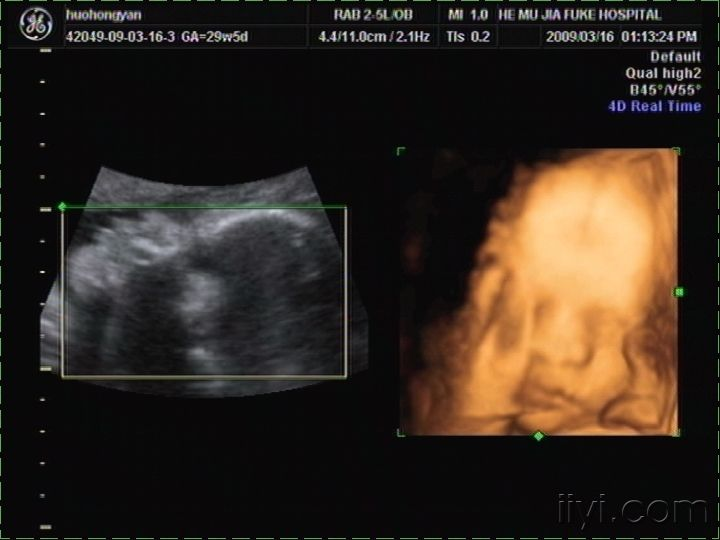

四维彩色超声诊断仪是目前世界上最先进的彩色超声设备。

在三维超声图像的基础上加上时间维度参数,能够实时获取三维图像,

超越了传统超声的限制,对人体无伤害。

四维彩超能够显示宝宝的实时动态活动图像,通过超声探头,

可以看到胎儿的眼睛、鼻子、嘴巴……宝宝伸出小手,好像在跟妈妈打招呼,继而咧嘴微笑。

当这个画面出现在彩超屏幕上时,妈妈和宝宝通过影像无声地交流,也是在出生前的第一次相遇。